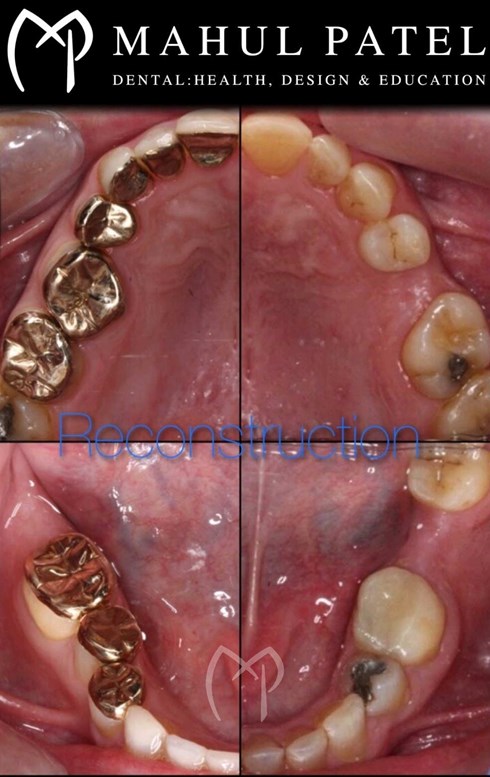

• Provision of full mouth reconstruction (fixed, removable and implant)